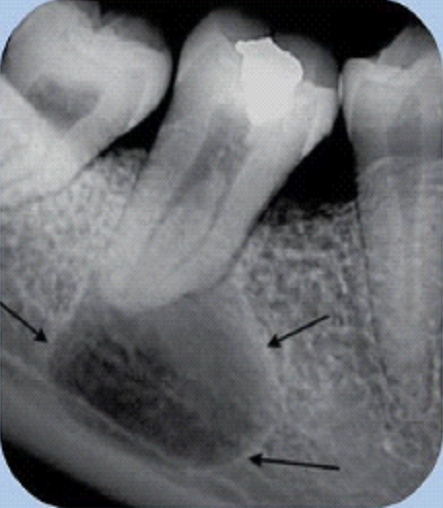

Mesmo quando o paciente não apresenta sintomas, o tratamento de canal pode ser necessário. Infecções pulpares podem evoluir de forma silenciosa, formando lesões na ponta da raiz, que comprometem o osso ao redor do dente e podem afetar dentes vizinhos (ESTRELA et al., 2014).

Quando essas lesões evoluem, o tratamento se torna mais complexo, podendo exigir cirurgias maiores, com maior custo, maior dificuldade técnica e tempo de recuperação mais prolongado. Por isso, o diagnóstico precoce e o tratamento adequado são fundamentais para evitar complicações.